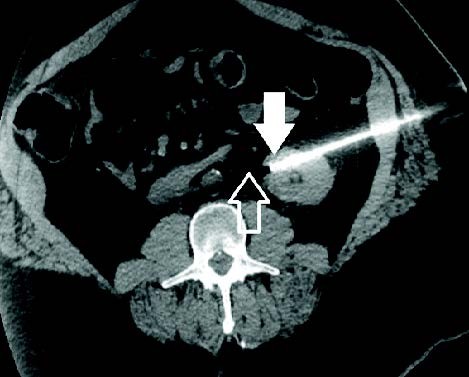

Usando la trayectoria de la aguja para proteger estructuras críticas

Un hombre de 53 años presentó un CCR endofítico de 2.5 cm x 2.3 cm en el aspecto anterior del polo inferior del riñón izquierdo. Se realizó crioablación con una aguja IceForce™ 2.1 CX. La punta de la aguja se apuntó hacia el uréter ya que el hielo letal solo se extiende 5 mm más allá de la punta de la aguja. El paciente fue dado de alta el mismo día y las imágenes de seguimiento demostraron que no había enfermedad residual o recurrente 12 meses después de la ablación.

AJ Gunn, MD | Universidad de Alabama en Birmingham | Birmingham, AL